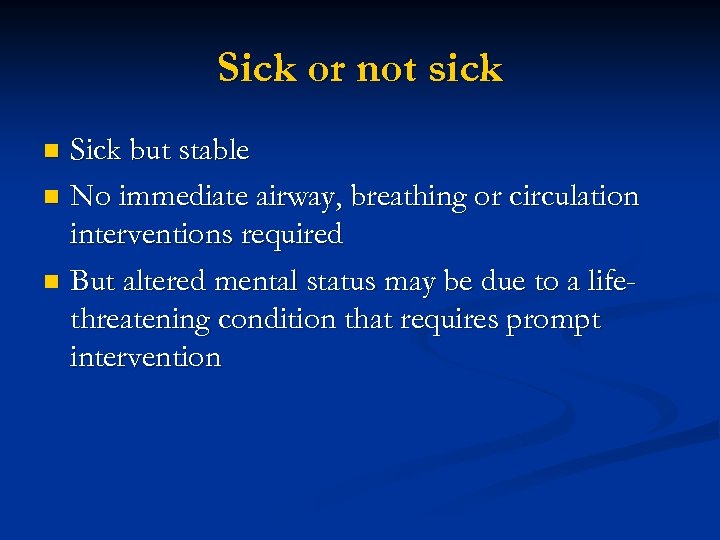

Sick or not sick Sick but stable n No immediate airway, breathing or circulation interventions required n But altered mental status may be due to a lifethreatening condition that requires prompt intervention n

Sick or not sick Sick but stable n No immediate airway, breathing or circulation interventions required n But altered mental status may be due to a lifethreatening condition that requires prompt intervention n